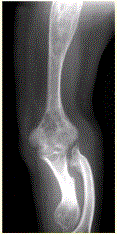

问题 患者男,22岁,长期存在骨和关节变形,近期出现右肘关节疼痛,进行性加重。行右肘关节X线正侧位片检查,见下图。 病变显示的征象包括

选项 A.累及干骺、骨干 B.累及多骨 C.髓腔内混杂密度影,病灶内含钙化 D.骨破坏形成软组织肿块 E.出现骨变形 F.受累骨未见骨膜反应

答案 ABCEF